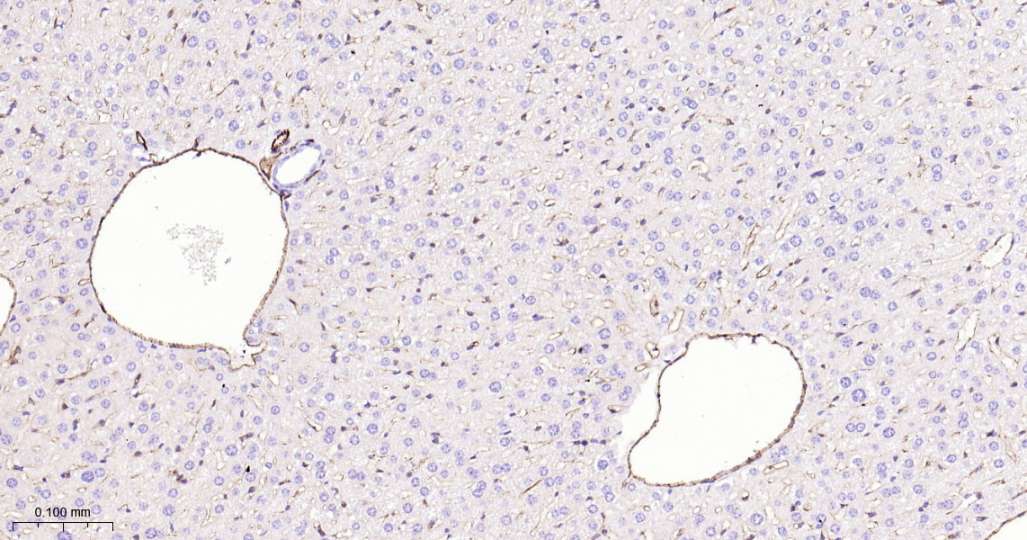

Immunohistochemical analysis of paraffin embedded Mouse liver tissue slide using IHC0599 (CD31 Kit).

Immunohistochemical analysis of paraffin embedded Rat liver tissue slide using IHC0599 (CD31 Kit).